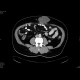

Scar hernia after laparoscopy

Laparscopic insertion of peritoneal catheter complicated by scar hernia which contains omentum and fluid.

Radiology image - Scar hernia after laparoscopy: Abdomen, Peritoneal cavity: CT - Computed tomography